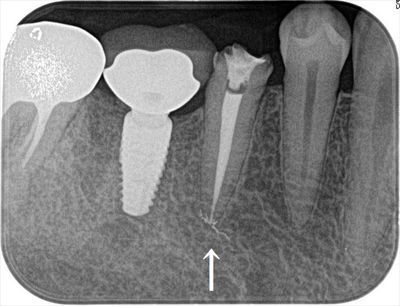

インプラント埋入時のレントゲン写真です。(2019.10.23)

根管充填後のデンタルレントゲン写真です。

インプラントにはジルコニアカスタムアバットメントとレジン製の仮歯をセットしています。

臨床的には誰が見ても到達していることが判るような根管充填であることが重要と考えます。

根尖まで到達して安堵する瞬間です。